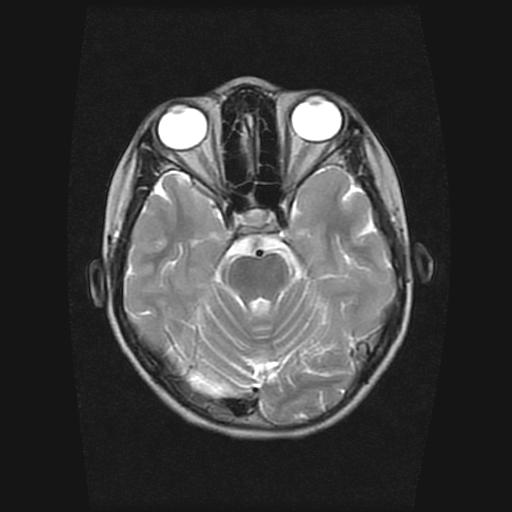

标题: PED0378:女孩9岁,癫痫,看能否停药 [打印本页]

9岁女孩,三岁时诊断为癫痫,一直服丙戊酸钠,现患者一般情况良好,家长复查核磁片,看能否停药..

巨脑回

未见异常信号灶.

未发现异常信号。